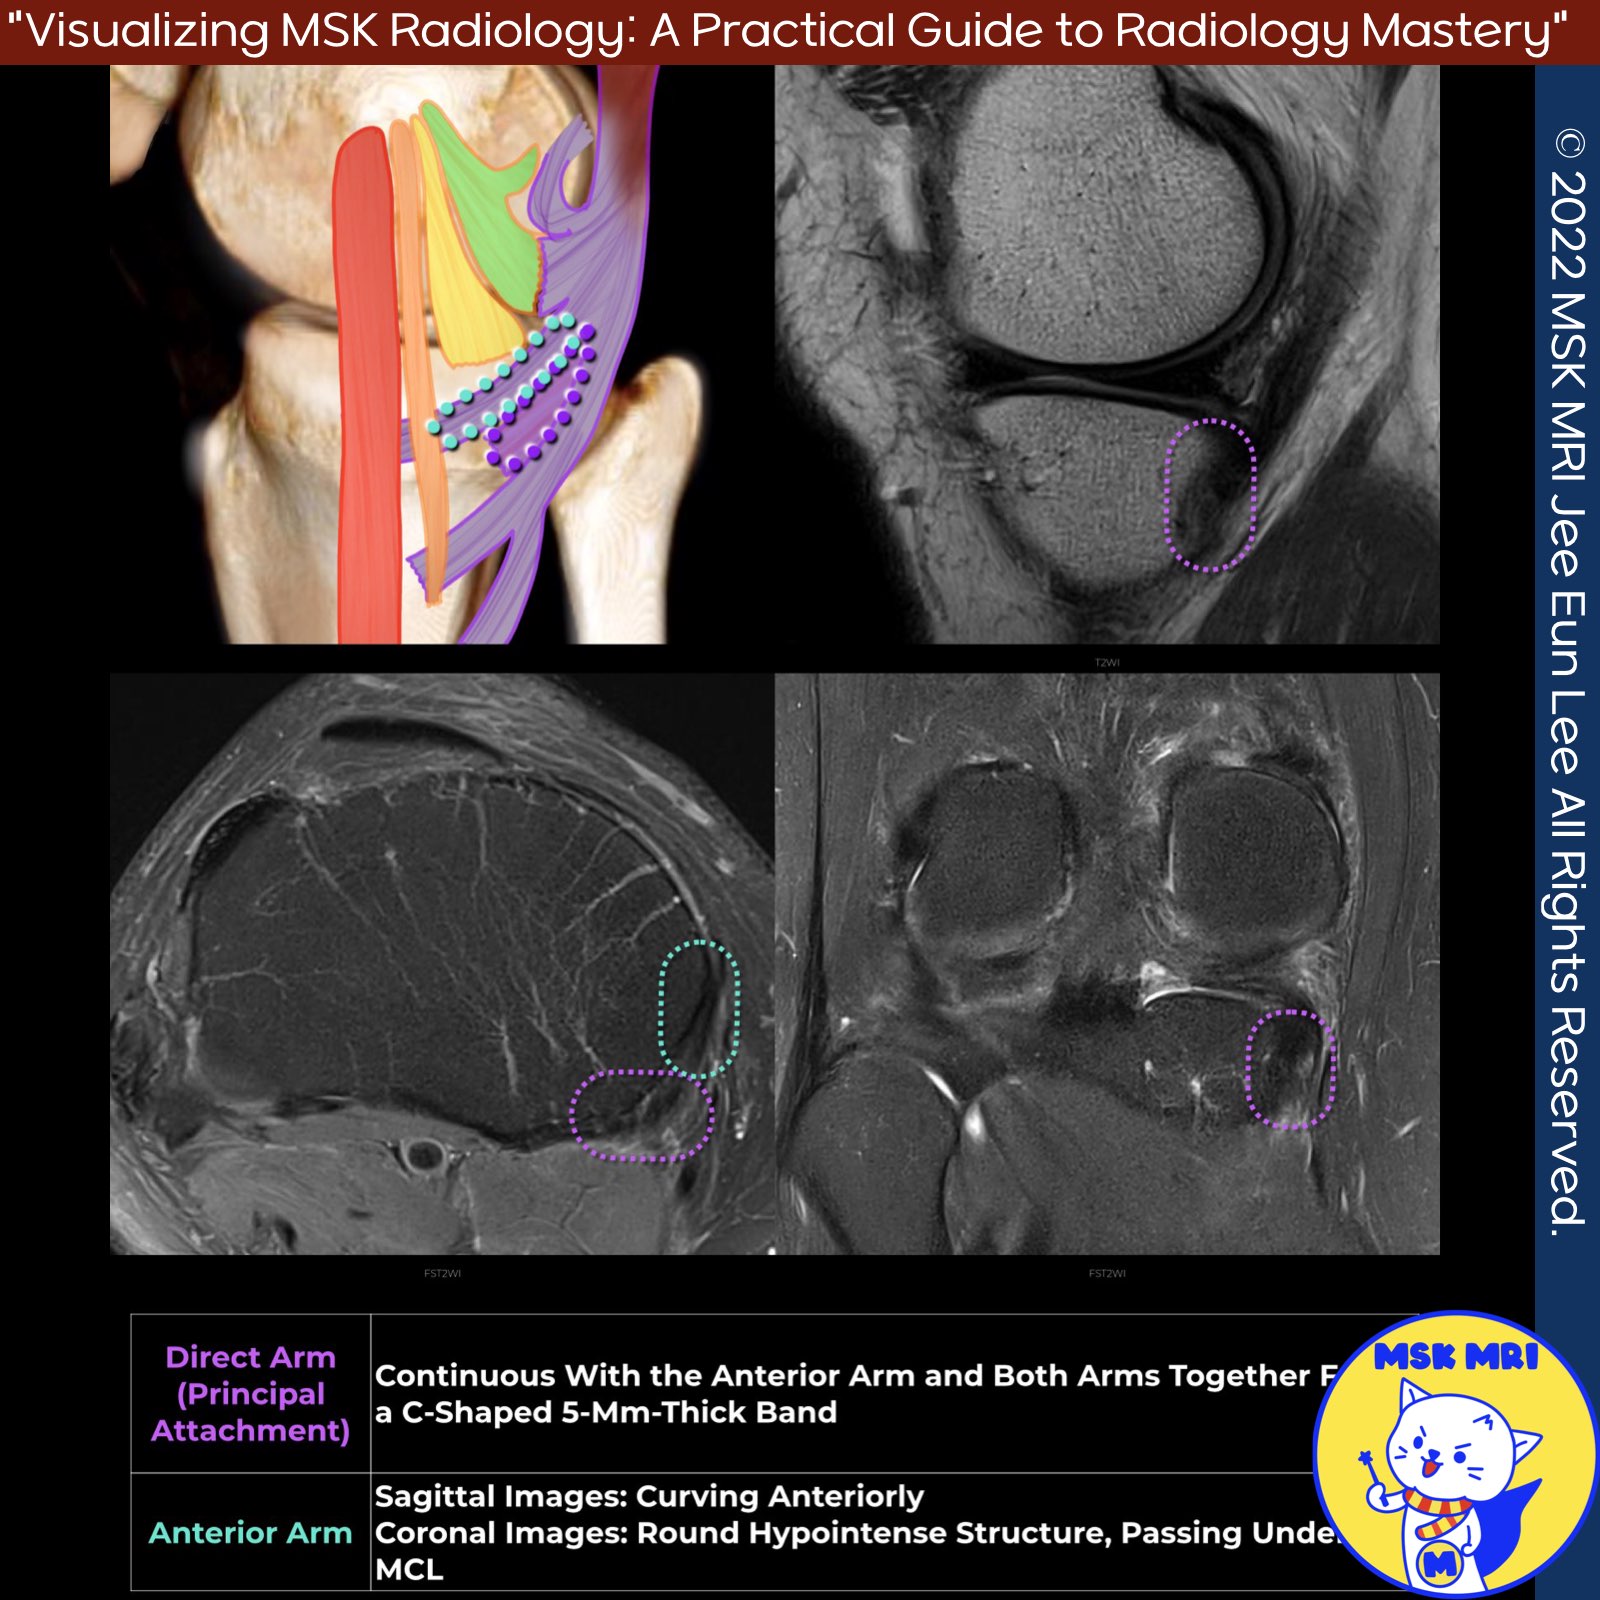

1️⃣Direct Arm (Principal Attachment):

- Attaches directly to the posteromedial aspect of the tibia, just distal to the joint line, in a groove known as the tuberculum tendinis.

- Forms a C-shaped, 5-mm-thick band with the anterior arm along the posteromedial tibia, difficult to distinguish from each other.

- Exhibits hyperintensity at its insertion site on MRI, which may be due to fat accumulation or magic angle artifact, and is not abnormal.

2️⃣Anterior Arm (Tibial or Reflected Arm, Pars Reflexa):

- Inserts into the medial proximal tibia, superior to the superficial MCL, and under the POL.

- Seen on peripheral medial sagittal images curving anteriorly and on coronal images as a hypointense structure adjacent to the medial tibia.

- Magic angle artifact noted in its thicker posterior portion.